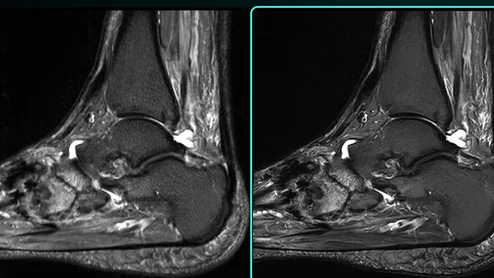

This is a collection of radiology imaging showing various presentations of thyroid nodules.